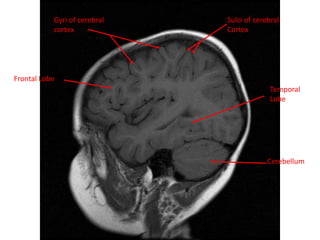

MRI BRAIN :SAGITTAL SECTIONS

White Matter

Cerebellum

Grey Matter

Frontal Lobe

Parietal Lobe

Temporal Lobe

Lateral Sulcus Occipital Lobe

Gyri of cerebral

cortex

Sulci of cerebral

Temporal

White Matter Cerebellum Grey Matter FrontalLobe Parietal Lobe Temporal Lobe Lateral Sulcus Occipital Lobe

Gyri of cerebral cortex Sulciof cerebral Cortex Cerebellum Frontal Lobe Temporal Lobe